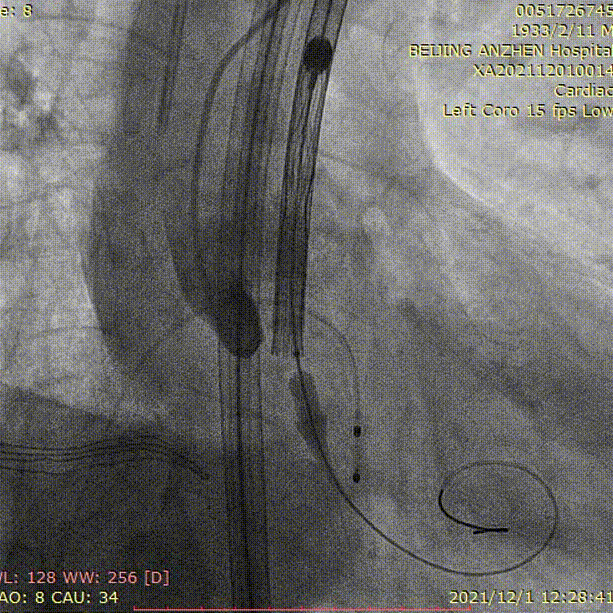

沿Super stiff导丝将65cm长22F鞘管(GORE DRYSEAL FLEX)缓慢送至升主动脉(视频2)。将6FAL2.0造影导管送至升主动脉,导丝跨瓣成功后,将塑形好的Lunderquist导丝送至左心室内,送入VitaFlow 30mm瓣膜(视频3)。精准定位瓣膜位置(视频4),在180次/分起搏下释放瓣膜(视频5),将输送系统及鞘管同步缓慢回撤至降主动脉,回收并撤出输送系统(视频6)。主动脉根部造影显示瓣膜形态良好,轻度瓣周漏(视频7)。瓣膜释放后,心电监护提示三度房室传导阻滞,穿刺右侧锁骨下静脉,送入主动电极并固定于室间隔右室侧,体外固定并连接脉冲发生器,程控起搏频率为70次/分,起搏稳定(视频8)。应用ProGlide缝合右股动脉穿刺部位。术后患者即刻苏醒,安全返回普通病房。

65cm鞘管(GORE DRYSEAL FLEX)送至升主动脉

送入VitaFlow 30mm瓣膜